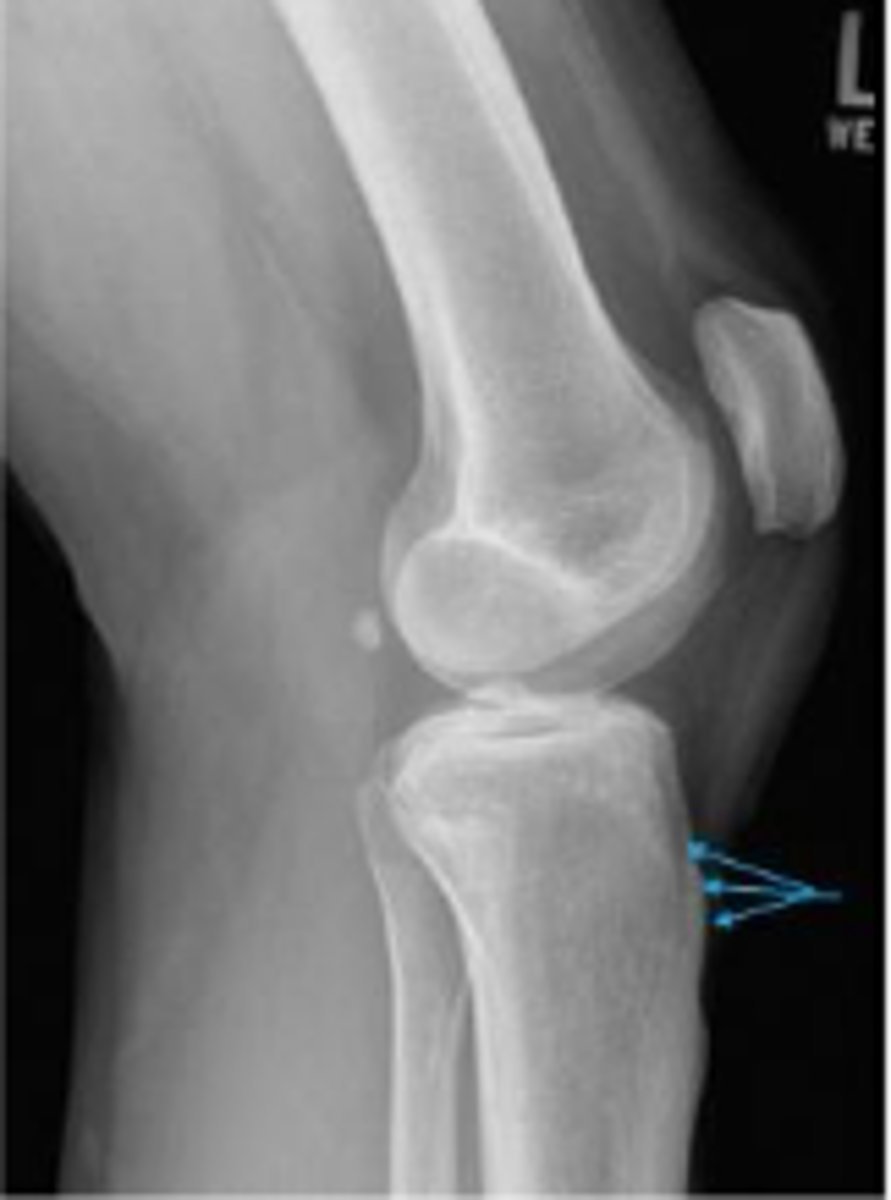

Medial oblique of the left knee

What is radiographic view?

Lateral oblique of the left knee

Lateral tibiofemoral alignment of the left knee

What is the assessment?